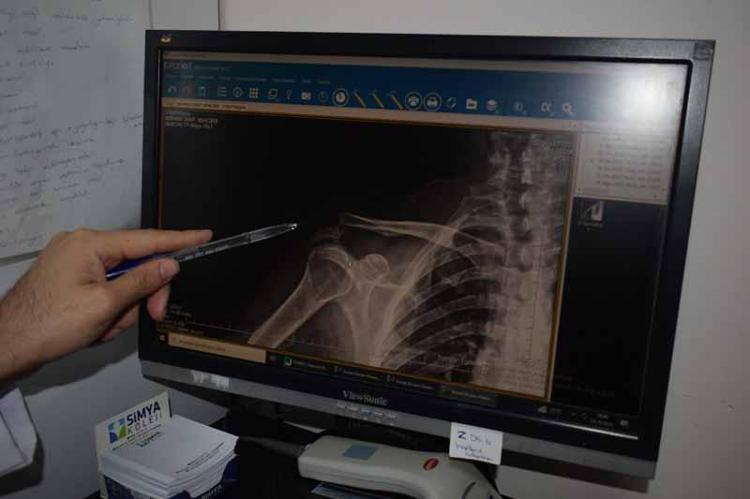

Kentteki bir kortta düştükten sonra omzunda çıkık oluşan Rençber’e, başvurduğu bazı merkezlerde yaş nedeniyle ameliyat önerilmedi. Batman Eğitim ve Araştırma Hastanesi Ortopedi ve Travmatoloji Uzmanı Dr. Mehmet Yavuz Başer’in değerlendirmesi sonrası hasta ameliyata alındı. Rençber’in omzuna kemik yapısına uyumlu, nadir kullanılan özel bir plak takıldı. Ameliyatın ardından fizyoterapi süreci başlatılan hasta, ağrılarının azalmasıyla günlük hareketlerini yapabilir hale geldi ve taburcu edildi.

Ameliyatın başarılı geçtiğini ifade eden Ortopedi ve Travmatoloji Uzmanı Dr. Mehmet Yavuz Başer, “Genelde gençlere ameliyat önerilirken bu hastamıza yaşından dolayı ameliyatlarla ilgili bazı sıkıntılar olduğu anlatılmış. Biz filmlerini gördük. Kendisiyle konuştuk.

Muayenesini yaptık. Sosyal olarak aktif birisi olduğu için ameliyat kararını daha uygun gördük. Ameliyatı çok şükür güzel geçti, başarılı geçti. Nadir kullanılan bir plaktan kullandık. O da hastamıza tam olarak uydu.